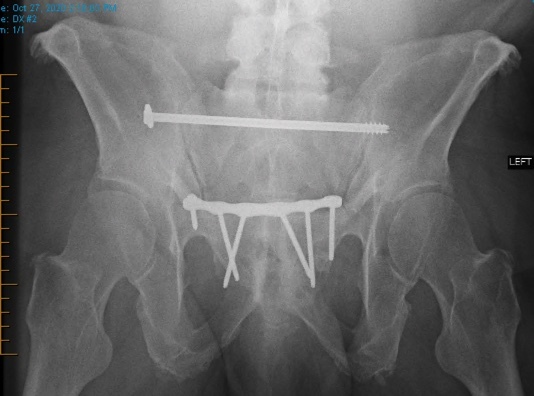

Chart review was undertaken to obtain basic demographic variables such as age, sex, smoking and diabetic history. Injury radiographs were reviewed to determine fracture type and Young-Burgess fracture classification. Preoperative and postoperative radiographs are demonstrated in figures 1A, 1B, 2A and 2B. Operative records were reviewed to determine which patients underwent screw removal and if any adverse intra-operative events occurred. Hospital charts and clinic charts were reviewed to document any postoperative complications and record pre and postoperative visual analog pain scales.

Posterior pelvic ring fixation with SI or TITS fixation is a well-accepted, successful means of fixation with good outcomes. Despite its widespread utilization, a paucity of publications exists on the indications and results of implant removal (Abumi et al. 2000; Culemann et al. 2004; Gänsslen, Hüfner, and Krettek 2006; Chip Routt, Simonian, and Mills 1997). Several case reports have demonstrated the proximity of neurovascular structures to these screws and demonstrated the possible risks associated with screw removal (Ebraheim et al. 1997; Mirkovic et al. 1991; Chip Routt, Simonian, and Mills 1997; Templeman et al. 1996). Figure 3 presents a diagram showing the proximity of neurovascular structures most likely to be damaged during placement or removal surgery.